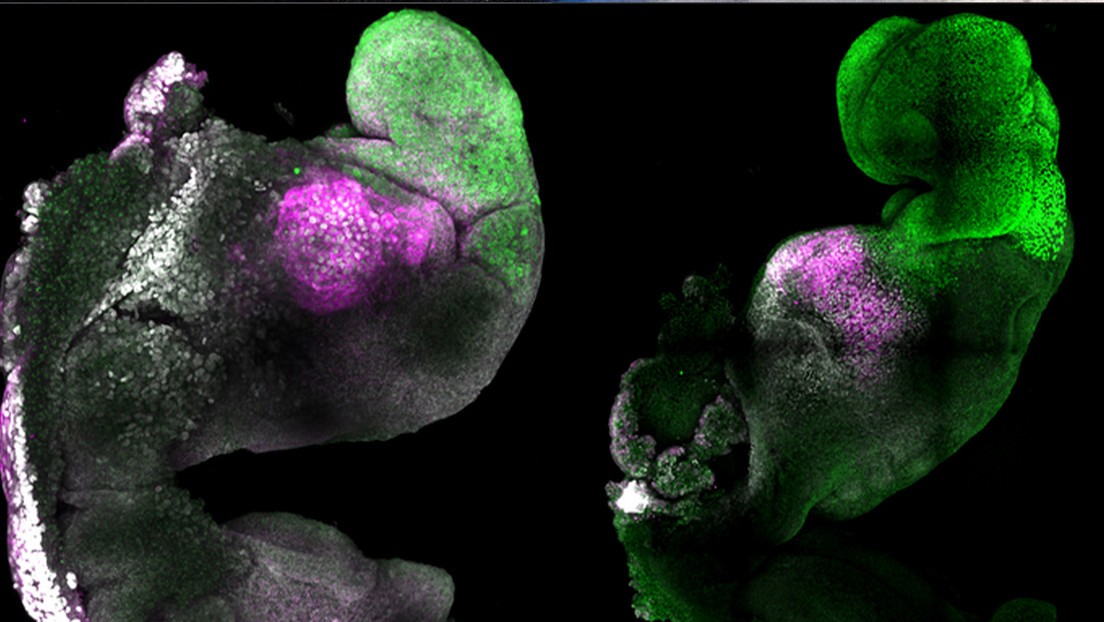

Los resultados de la investigación permitiría a los investigadores comprender por qué algunos embriones fallan, mientras que otros culminan en un embarazo saludable.Para recrear las primeras etapas de la vida en mamíferos, investigadores de la Univer...